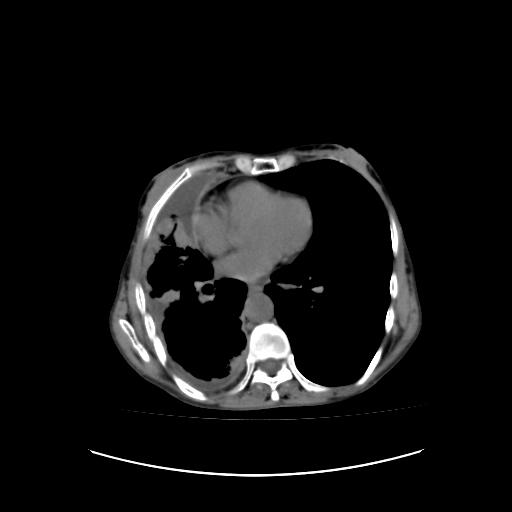

标题: CT16930:女 59 胸痛6个月 胸水脱落细胞学见瘤细胞 [打印本页]

标题: CT16930:女 59 胸痛6个月 胸水脱落细胞学见瘤细胞

右侧胸廓塌陷,右侧胸膜广泛增厚并见多发胸膜结节,右侧少量胸腔积液并包裹。

胸膜转移瘤  包裹性胸腔积液  肺内转移

右胸腔结节均考虑来自胸膜(部分来源于叶裂),考虑胸膜间皮瘤或转移瘤.